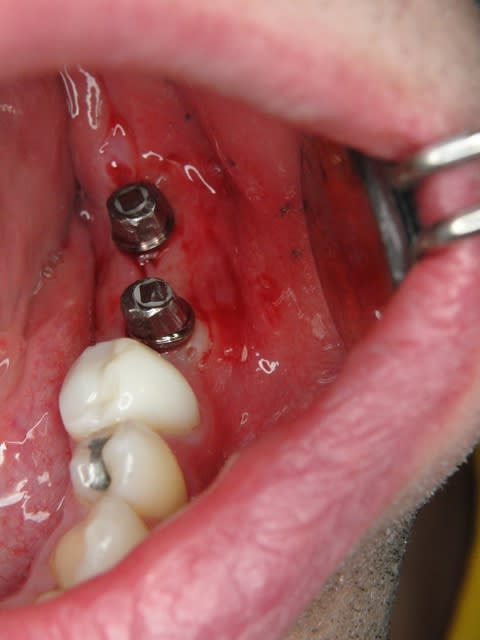

Maintenant concernant la demande de scans : je poste ce cas, une patiente vient me voir avec son scan car elle a consulté d'autres "spécialistes" et on lui refuse la pose d'implant secteur 4 où alors avec greffe préalable..Ca se discute..pas de temps à perdre je sais faire autrement..

Avec la chir trans gingivale technique MIMI ( Oui..un post sur la technique bientôt ..) j'ai pu placer deux 3,5/8mm..aurai je eu le meme résultat avec un lambeau..j'en doute..Les couronnes sont en titane. Recul clinique 2 ans ras. Simple efficace rapide moins onéreux satisfaisant pour le praticien et la patiente..